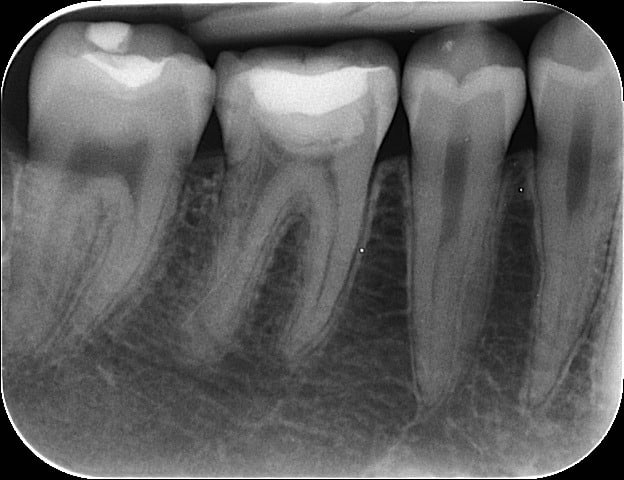

Voilà les radios apres obturation.

Il n'y a pas eu de fusée de gutta...ouf!

J'ai mis vraiment très très peu de ciment et en distal j'ai renforcé la dent avec un collage avec du composite flow. Et puis j'ai terminé avec un composite classique en occlusal.

La patiente est prévenu que l'avenir de cette dent est incertain mais ravie qu'on ai essayé de tout faire pour la sauver.

PS: désolé pour la dernière radio à l'envers...

Radio pré-op= furcation (concavité) très prononcé avec 2 racines distales distincts.